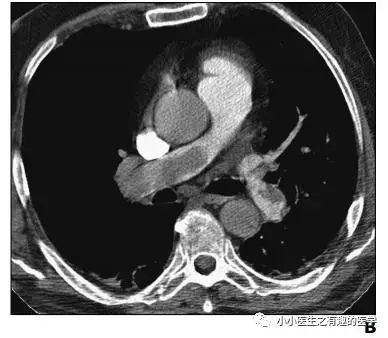

不光是肺栓塞,连主动脉夹层,都发现了。

牛。我来标记一下。

老外报道一例患者,门诊急诊CT平扫发现肺栓塞,但是患者危重,再次外出做增强CT很危险,别人直接高分辨CT诊断肺栓塞,直接治疗,病情缓解再出去检查。在中国,你懂的(抱歉:有些文献*载下**要钱,穷,没有*载下**到)。